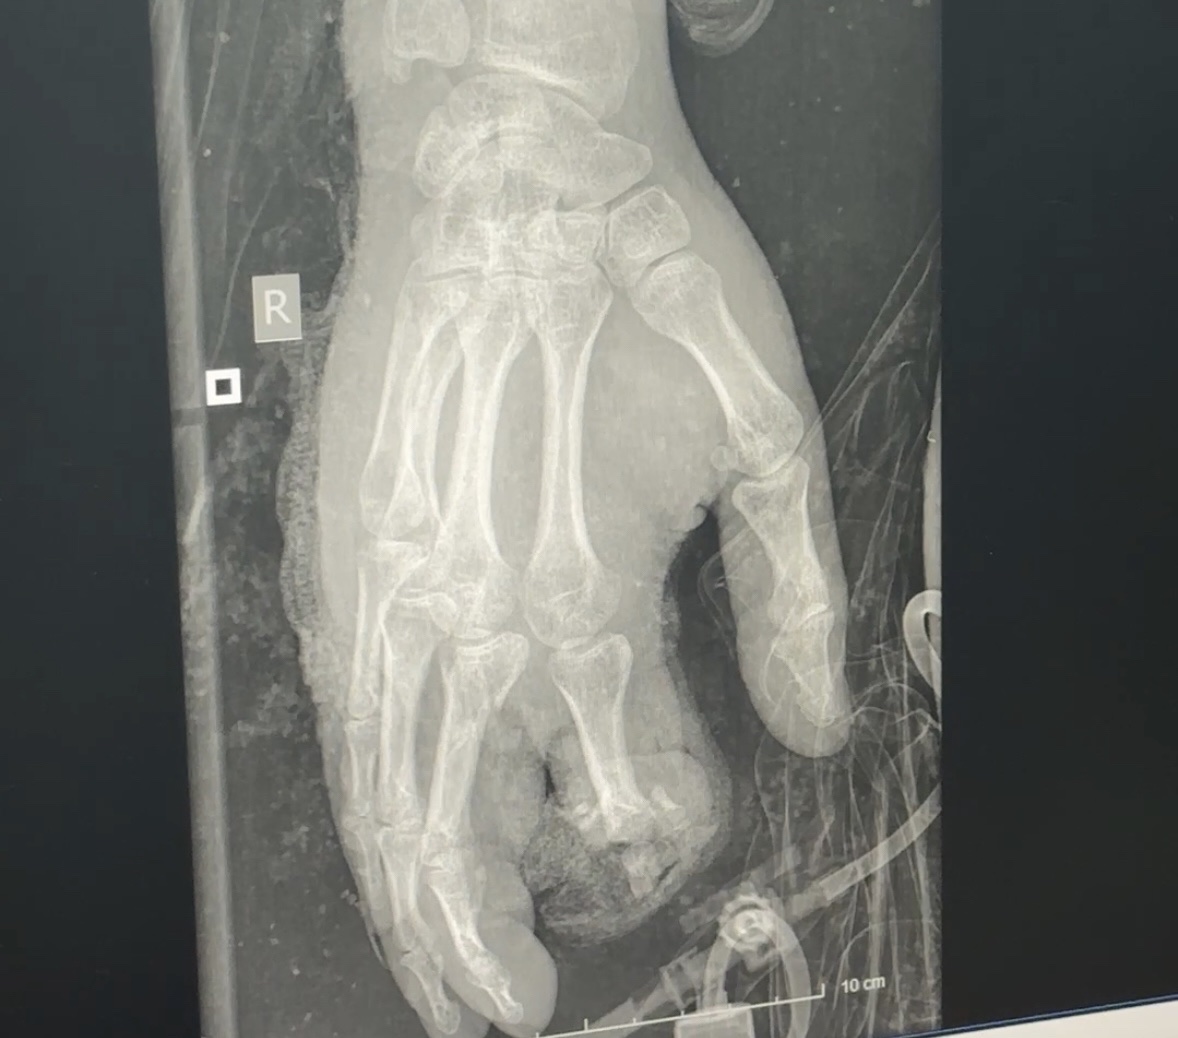

Bệnh nhân bị giập nát bàn tay sau tai nạn pháo nổ – Ảnh: BVCC

Đáng chú ý là trường hợp bệnh nhân 15 tuổi (trú tại Thái Nguyên) được đưa vào viện trong tình trạng giập nát cẳng bàn tay hai bên, bỏng vùng mặt, cẳng chân và thành trước ngực. Các tổn thương nghiêm trọng đe dọa trực tiếp tính mạng và khả năng lao động lâu dài của bệnh nhân.